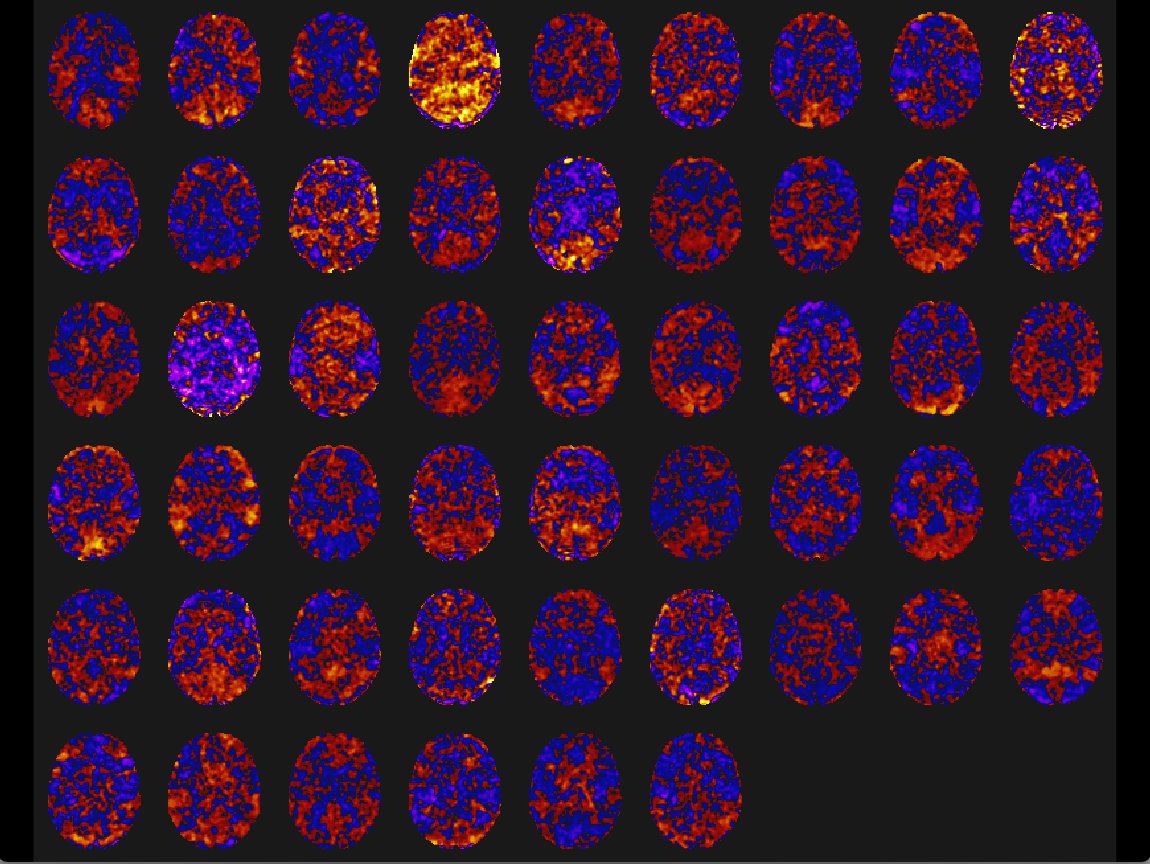

- First level analysis (Group ICA and PCA analyses) was performed. Images of the process are in the Data section.

Exploratory fMRI analysis results - 1st Level Analyses (basic ROIs, Group ICA and PCA)

Alongside DWI (Diffusion Weighted Imaging), which allowed me to observe and analyze the structural connectivity and integrity of the MND patients, I used fMRI to analyze the different connectivity components that measured brain activity over a set period of time. By using ds005874 from OpenNeuro, I had the ability to sufficiently analyze these separate modalities. Measuring brain activity told me exactly where the different areas of hypoconnectivity and, interestingly, hyperconnectivity were. From these findings, I was able to understand the areas that would be of interest to target with my pharmaceutical approach.

Group ICA - A tool in the CONN Toolbox that splits brain regions into independent components for analysis. Shows common connectivity across brain regions.

Group PCA - Used PRIOR to Group ICA to reduce the dimensionality between Voxel-Voxel connectivity matricies. Allows for easier calculations in ICA.

Results of Group ICA/PCA

Shows mini movie map for all 51 patients in an ICA component. The variation of connectivity is filtered by selected components.

GLM pictures viewed in the CONN toolbox as Group ICA (group results) visualized for chosen ICA component.